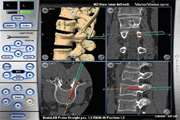

ارایه روش جدید جایگذاری پیچ در مهره های کمری به کمک انطباق سطوح تصاویر استریو حین عمل و تصاویر CT قبل از عمل ستون فقرات 1404/08/12 - 11:47